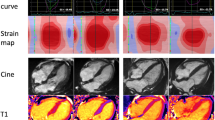

Top Panel: Echocardiography findings in a patient with advanced cardiac amyloidosis. (a) Parasternal long axis view and (b) four chamber view showing concentric left ventricular hypertrophy (c) pulse wave Doppler showing restrictive left ventricular inflow pattern (d) strain pattern characteristic of an infiltrative process. Bottom Panel: CMR findings in a patient with advanced cardiac amyloidosis. (e) Four chamber steady state free precession cine demonstrating left ventricular hypertrophy (f) corresponding native T1 map showing a T1 value of 1150 ms in the basal inferoseptum (g) corresponding T2 map showing a T2 value of 54 ms in the basal inferoseptum, within normal limits (h) corresponding phase sensitive inversion recovery reconstruction showing transmural late gadolinium enhancement (i) corresponding extracellular volume map showing elevated value of 0.70

and informs upon tissue composition through its intrinsic capacity to define myocardial tissue characterization. The deposition of amyloid fibrils in the extracellular myocardial space leads to expansion of the extracellular volume, which is well visualized by the administration of gadolinium-based contrast agents, referred to as ‘late gadolinium enhancement’ (LGE). Gadolinium accumulates passively in gaps between myocardial cells giving rise to the appearance of diffuse subendocardial or transmural LGE in CA, in the presence of abnormal myocardial and blood pool gadolinium characteristics, a phenomenon that was recognized over 10 years ago. [35] LGE differentiates normal from abnormal myocardium, based on the assumption that there are remote regions of normal myocardium. However, this may not exist in diffuse infiltrative diseases such as CA, exposing an area for potential operator error whereby the operator may erroneously null the abnormal and not normal myocardium, carrying a risk of reporting ‘false negative’ examinations or ‘mirror images’ of the true pattern. [36] The LGE technique has matured over the years leading to the wide adoption of ‘phase sensitive image reconstruction’ (PSIR) which is a more robust and reliable technique than magnitude reconstruction with the primary advantage that it largely overrides the dependence on operator determined optimal null point and related errors [36]. With the PSIR LGE approach, 3 patterns of LGE have been recognized; none, sub-endocardial and transmural, and transmurality of LGE shows good correlation with the degree of myocardial infiltration. (Fig. 1) [36] An important drawback of LGE is that gadolinium-based contrast agents (GBCA) have been associated with nephrogenic systemic fibrosis (NSF), a serious and potentially fatal condition. Whilst the risk of developing NSF is strongly related to baseline renal function (being the highest when eGFR <30 mL/min), the underlying chemical structure of the contrast agent also plays an important role in determining risk. Recent guidelines from the American College of Radiology recommend the preferential use of Group II agents in patients at risk of NSF if clinically indicated, emphasizing the requirement for a balanced assessment of the risks of administrating GBCA against the risks of not performing a contrast scan. [37] Whilst the initial understanding was that the gadolinium ion remained in a chelated state after intravenous administration, multiple studies have demonstrated evidence of tissue retention, even in patients with normal renal function [38] including reports of involvement in neural tissue (dentate nucleus, thalamus, pons, and globus pallidus) [39,40,41] and bone tissue, [42] clinical implications of which are not fully understood. A further limitation of LGE is that it cannot be used to track changes in disease status over time due its non-quantitative nature.

These limitations can be overcome by the use of T1 mapping which directly measures an intrinsic signal from the myocardium, the longitudinal relaxation time, in a pixel wise manner. (Fig. 1) Native (pre-contrast) myocardial T1 tracks cardiac amyloid infiltration, markers of systolic and diastolic dysfunction and disease severity [43].

Native T1 is a composite signal, from both the extra and intracellular space. Following the administration of gadolinium contrast agents, from the ratio of pre and post contrast T1 and haematocrit, the signal from the extracellular space can be isolated with the measurement of the extracellular volume (ECV).

ECV is the first non-invasive method for quantifying the cardiac amyloid burden, and several studies have shown correlation with markers of disease severity in both types of CA. [22, 45] The ECV is globally elevated, often with values >40% and higher in ATTR than AL CA. (Fig. 1) Important benefits of ECV measurement in CA include its unique ability to measure the continuum of amyloid infiltration, to track markers of disease activity such as cardiac function, blood biomarkers and functional performance, to act as an early disease marker and to uniquely track changes over time. [45] For example, almost half of the patients in a studied cohort who achieved a good clonal response to chemotherapy in AL amyloidosis demonstrated evidence of regression of cardiac amyloid on ECV [46].

In conjunction with detailed morphological and functional assessments, tissue characterization by CMR provide a wholesome understanding of the multiple disease processes that exist within CA, transcending the concept of CA as a disease of solely infiltration. T2 relaxation time is a time constant representing the decay of transverse magnetization and detects oedema in various pathologies including but not limited to acute myocardial infarction, myocarditis, and Takotsubo cardiomyopathy. (Fig. 1) [47] Recently, T2 mapping in CA has added significantly to our understanding of CA as a heterogenous condition comprising multiple disease processes by demonstrating that T2 levels were higher in a cohort of patients with untreated AL CA compared with treated AL and ATTR CA, thereby showing oedema to have both important pathophysiological and prognostic roles [48•].